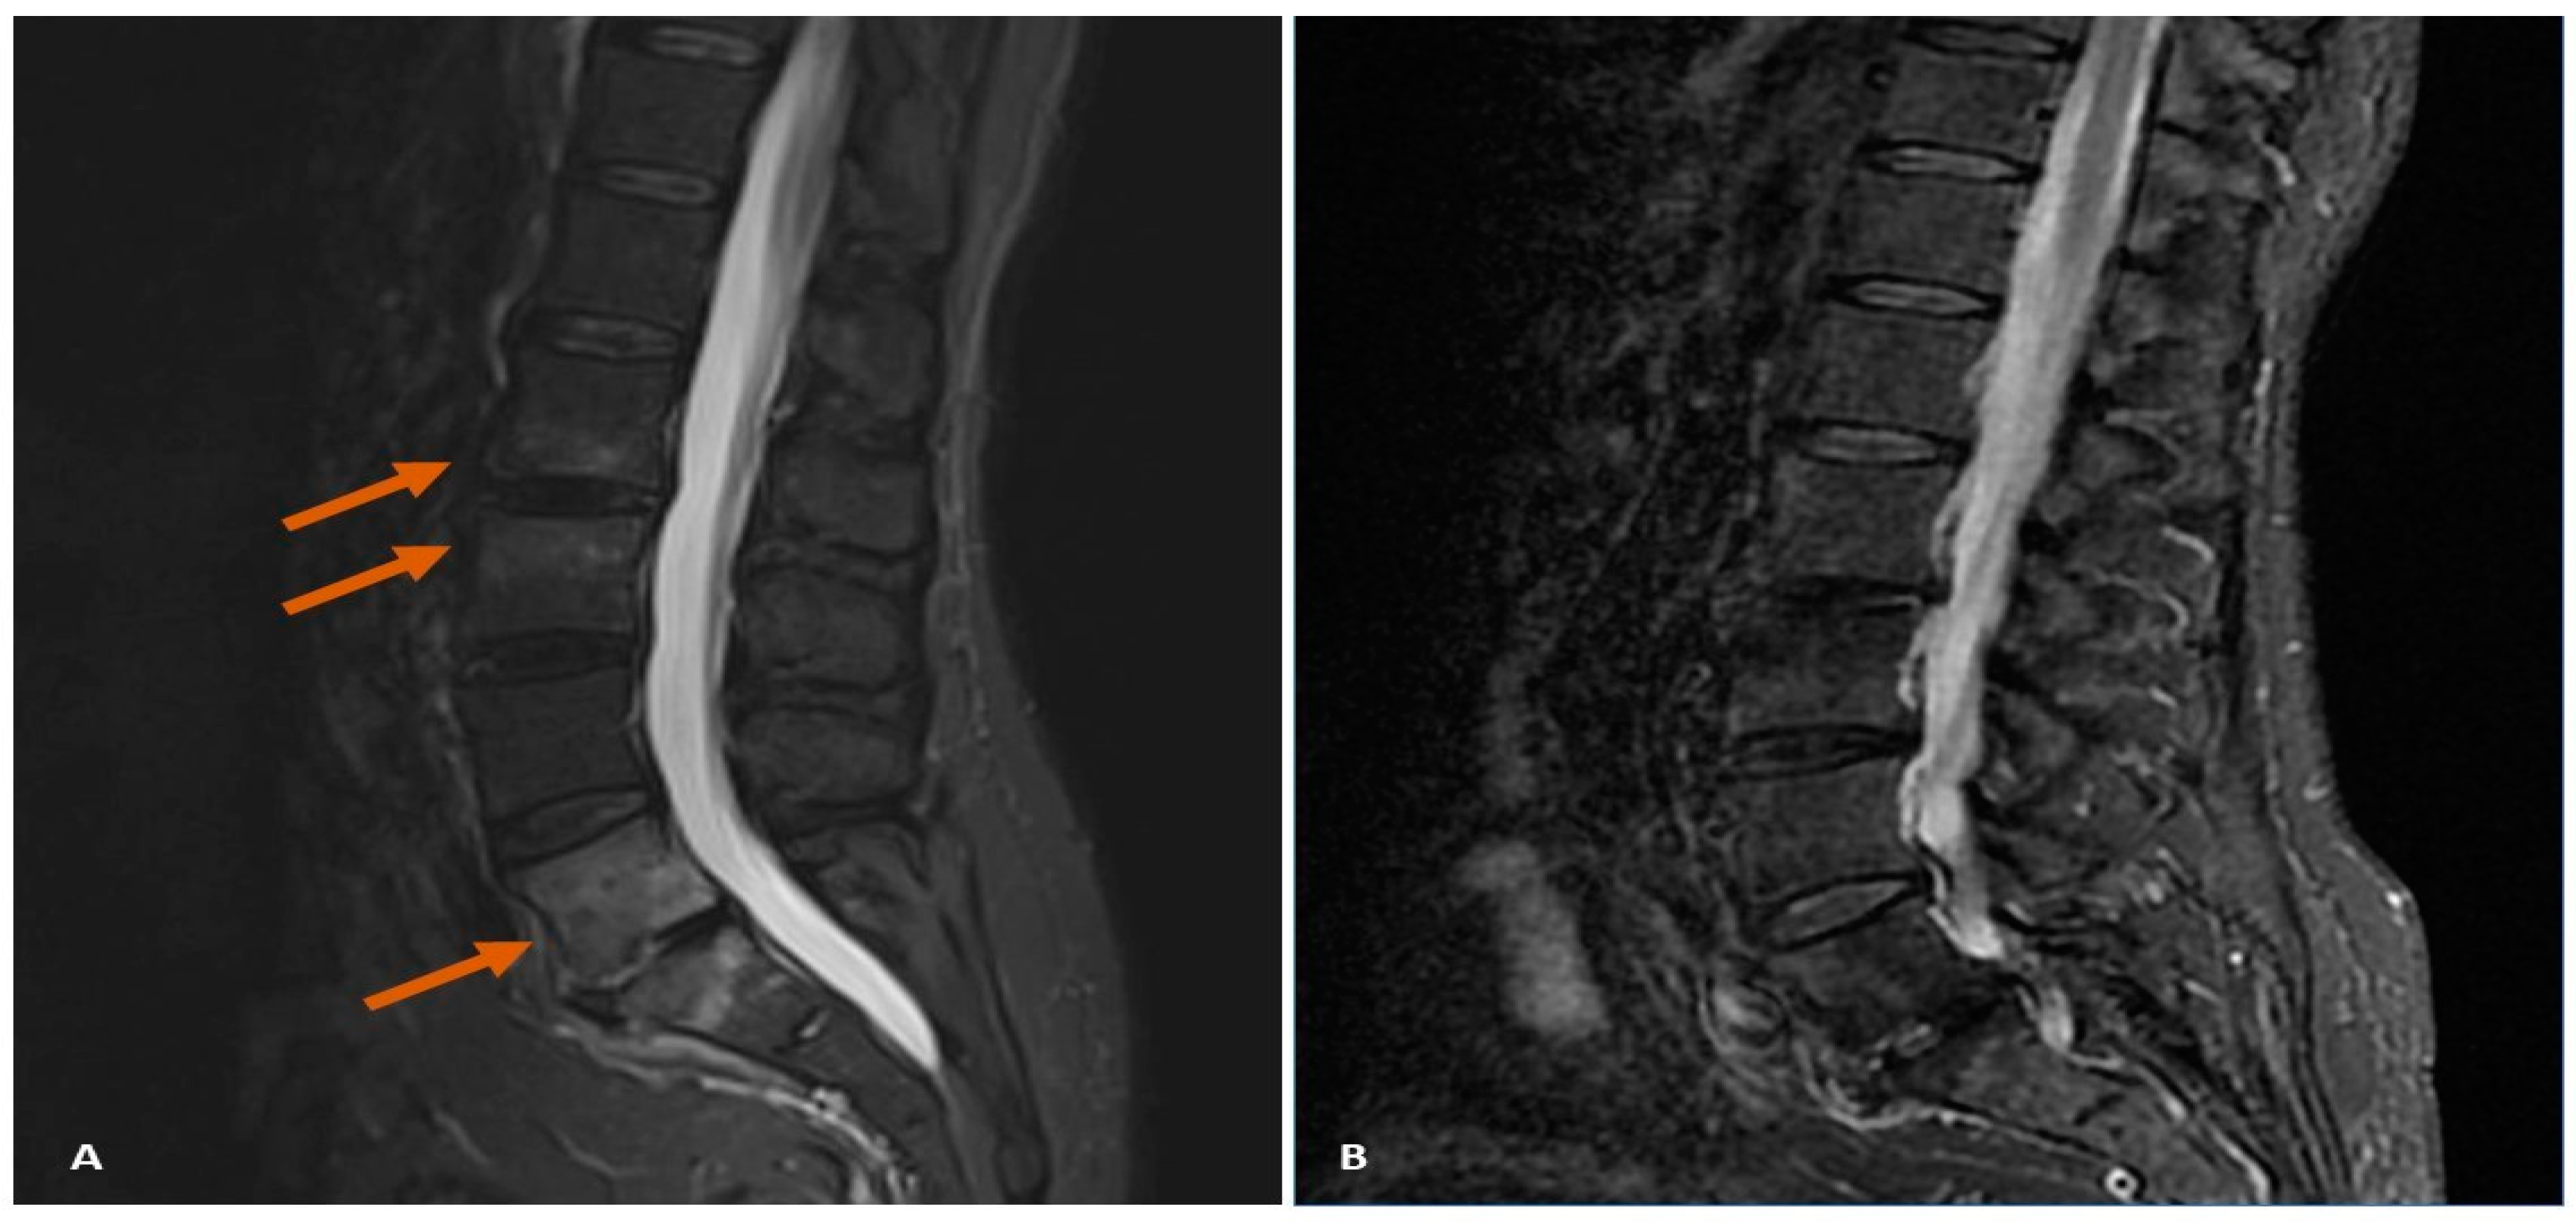

7.2. Case Study 2